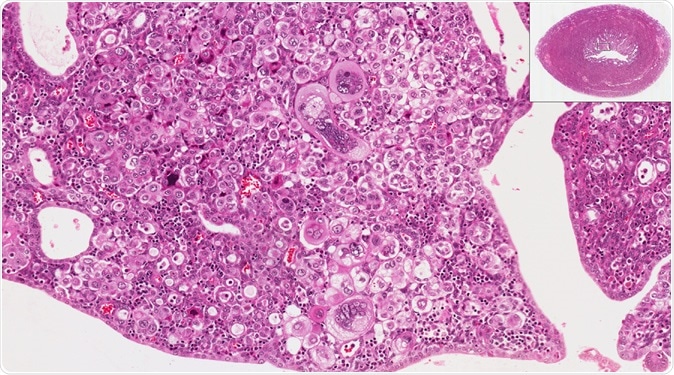

The new study from NYU Langone researchers provides an in-depth survey of the molecular players in endometrial cancer and suggests new treatment approaches. High and low power microscopic view of endometrium (uterus) to show endometrial cancer. Image Credit: vetpathologist / Shutterstock